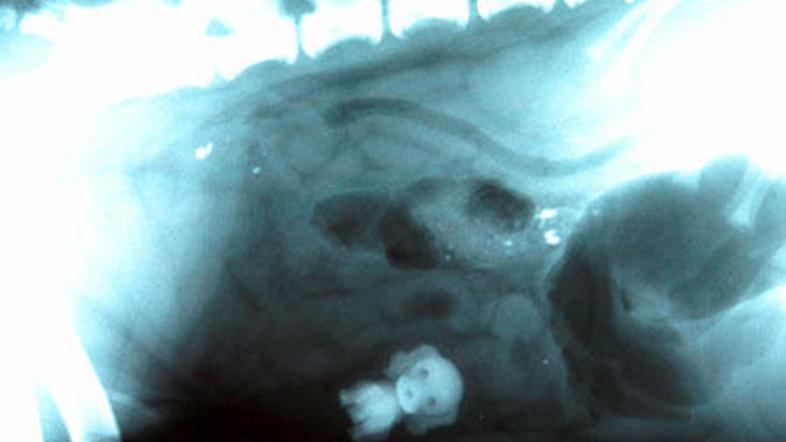

Tokrat vam v galeriji na ogled ponujam nenavadne rentgentske posnetke. Oglejte si, katere nenavadne predmete so pogoltnili ljudje ali celo živali.